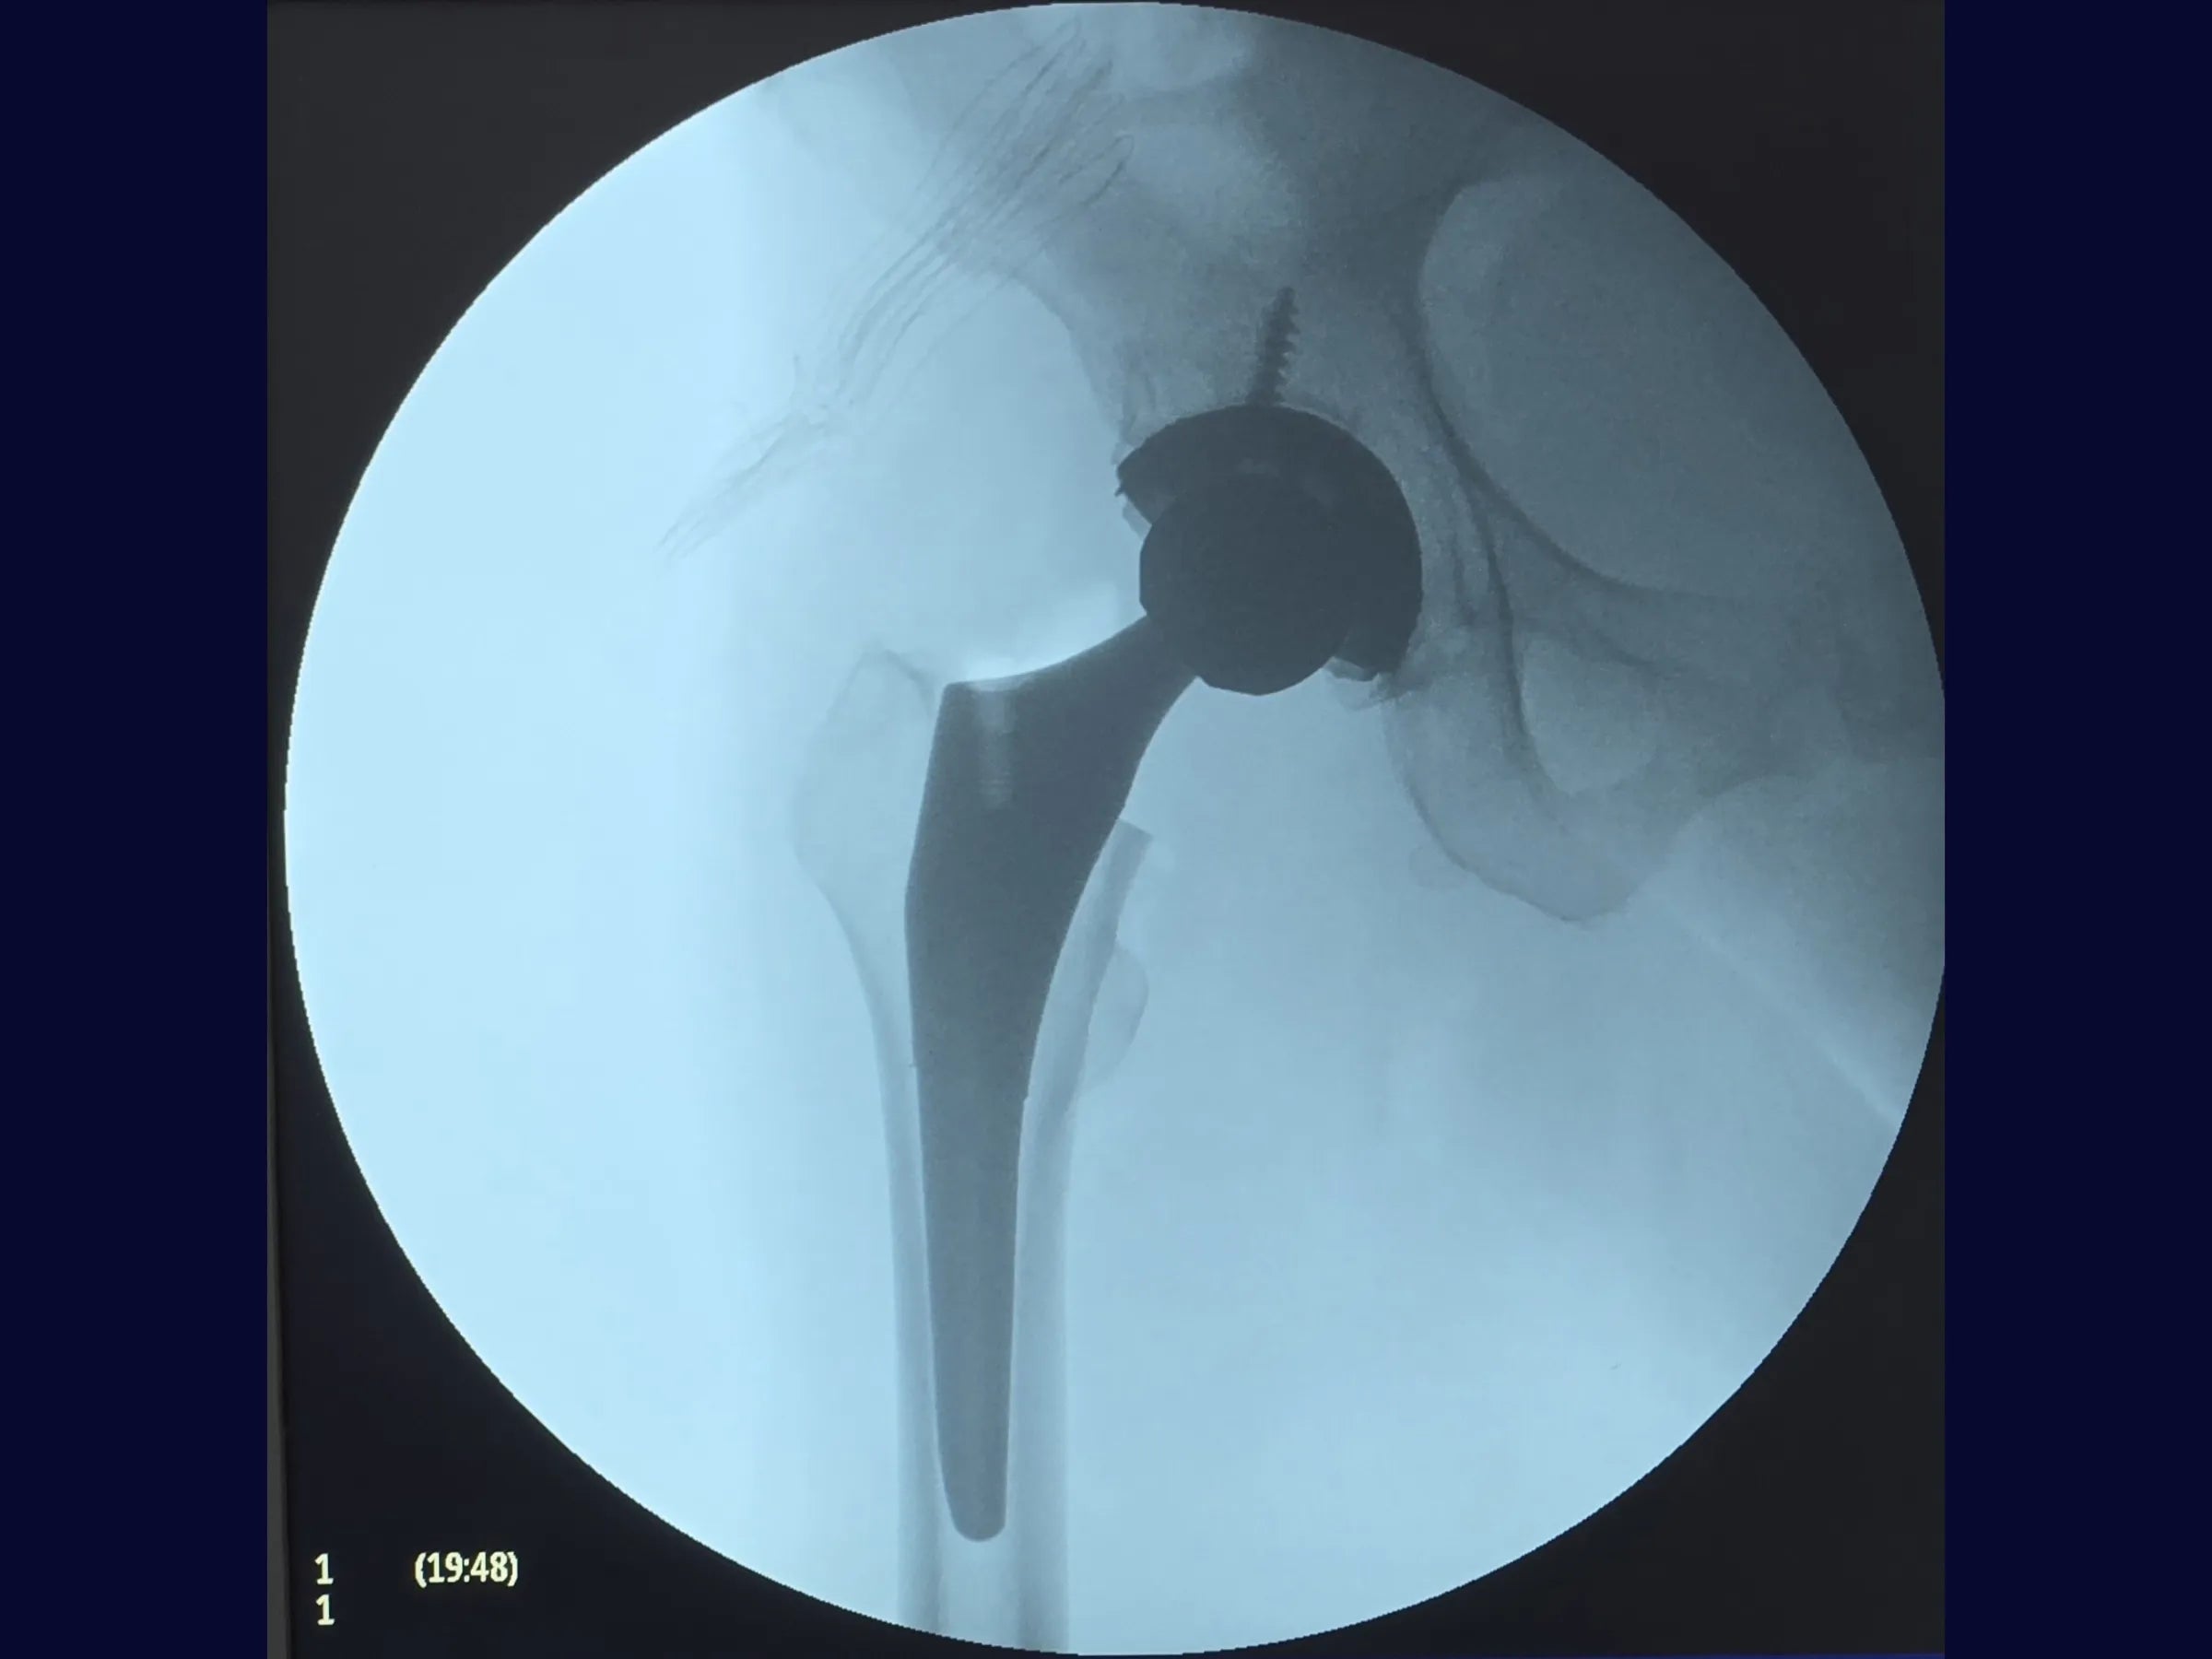

• Preparação acetabular com cup em press-fit e fixação póstero-superior com parafusos;

• Posicionamento do liner com lip de 10°;

- Press-fit acetabular confiável com fresagem circunferencial, parafusos direcionados ao teto e liner com lip de 10° póstero-superior para estabilidade aumentada;

- Protocolo de validação dinâmica com testes em flexão >90° e rotação interna, ajuste de tensão tecidual e verificação de comprimento antes da redução definitiva;

PDF Técnico Completo: inclui raio X, posicionamento do paciente, marcos anatômicos, instrumentais, critérios de estabilidade, algoritmos de decisão e cuidados pós-operatórios.